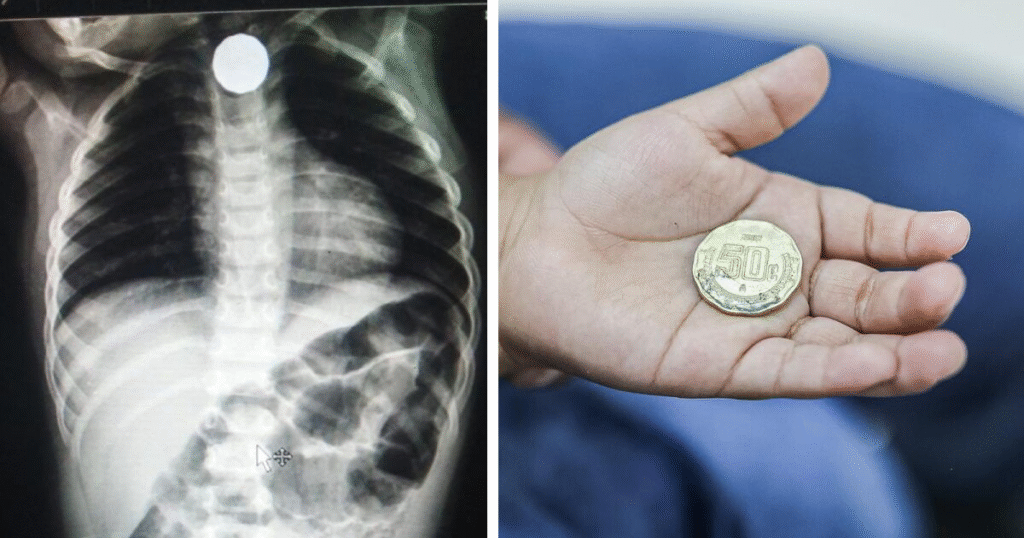

Una emergencia pediátrica movilizó al Hospital Regional Docente Materno Infantil “El Carmen” cuando una niña de 4 años se tragó una moneda de 10 céntimos. La menor fue atendida de urgencia por el equipo de cirugía pediátrica, que logró extraer el objeto alojado en su esófago con éxito.

El procedimiento consistió en una cirugía para extracción de cuerpo extraño. Luego de la intervención, la paciente fue llevada a la cama 15 de hospitalización, donde su evolución fue favorable. Horas después, fue dada de alta en buen estado de salud.

Imagen referencial